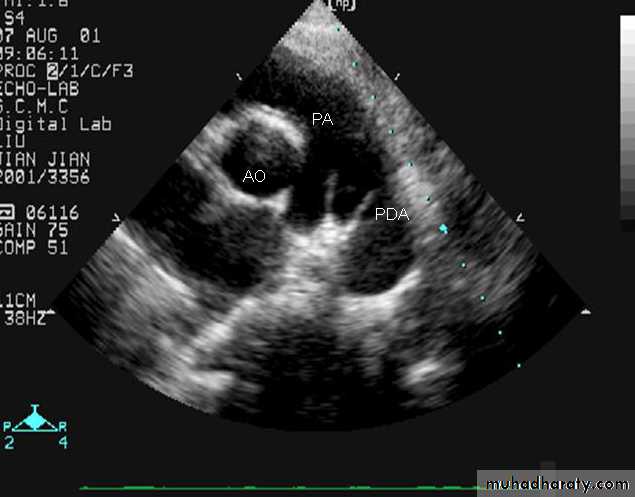

PATENT DUCTUS ARTERIOSUS (cont.)

Echo: is diagnostic2D echocardiogram can idendtify the PDA which can be confirmed by Doppler.